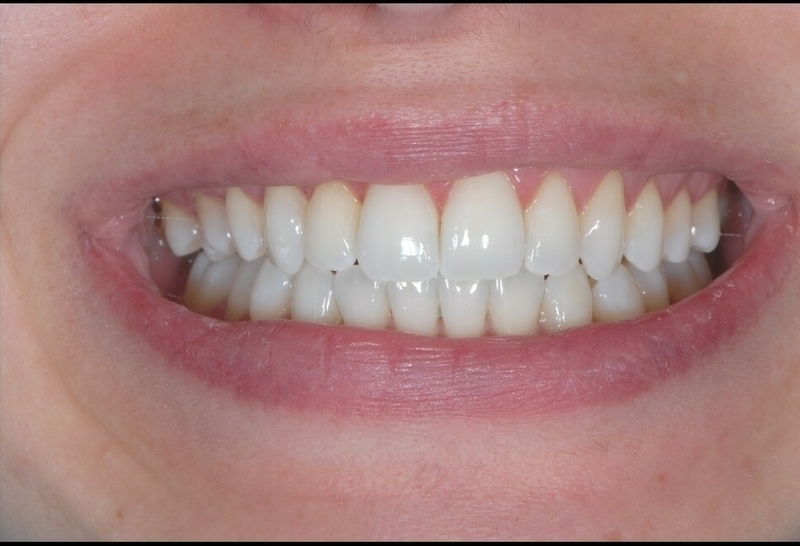

Avant

Après